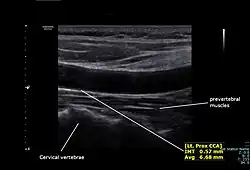

Left proximal common carotid artery intimal thickness (IMT) measurement and diameter by using doppler ultrasound

The condition and health of the common carotid arteries is usually evaluated using Doppler ultrasound, CT angiography or phase contrast magnetic resonance imaging (PC-MRI).

The intima-media thickness of the carotid artery wall is a marker of subclinical atherosclerosis and it increases with age and with long-term exposure to particulate air pollution. [9]